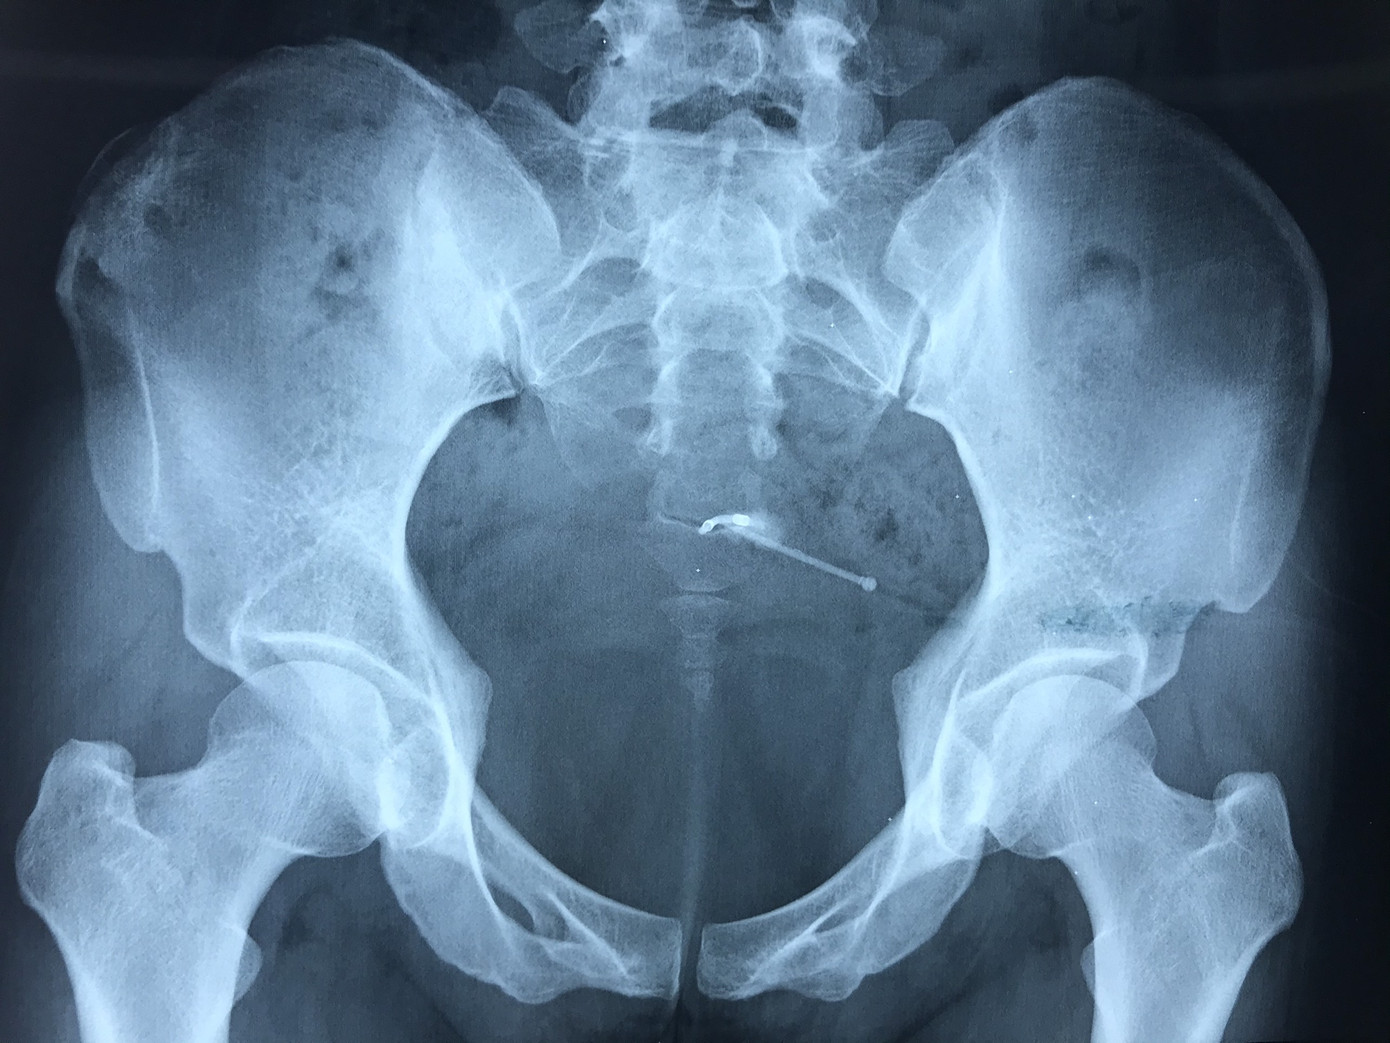

Vòng tránh thai chữ T "lạc" trong bàng quang. Đinh ninh rằng vòng đã bị tuột ra ngoài nên chị N. không đi khám. Tuy nhiên vài ngày nay, nữ bệnh nhân thường xuyên bị đau âm ỉ hạ vị kèm tiểu gắt, tiểu ngưng giữa dòng nên đã đến bệnh viện khám.

Trong quá trình phẫu thuật, phát hiện bệnh nhân còn có một dị vật khác đâm xuyên thành bàng quang tạo thành một khối đường kính khoảng 5mm. Tuy nhiên, do dị vật bám chắc vào thành bàng quang nên không thể lấy qua nội soi. Sau đó, các bác sĩ tiến hành chụp cắt lớp vi tính, kết quả ghi nhận đây là dụng cụ tránh thai lạc chỗ vùng ngoài tử cung cạnh thành trên, xuyên thành bàng quang, kích thước 3 cm.

Vòng tránh thai dài khoảng 4cm bao bọc chặt bởi các cơ trong bàng quang được lấy ra thành công. Các bác sĩ hội chẩn quyết định phẫu thuật lấy vòng tránh thai bị lạc chỗ. Tiến hành bộc lộ bàng quang, xẻ thành trước 5cm, xác định vị trí dị vật, xẻ mô bàng quang bóc tách đến vị trí chữ “T”. Ekip đã lấy ra thành công vòng tránh thai dài khoảng 4cm được bao chặt bởi các cơ xung quanh. Do đó, khi siêu âm không phát hiện được dị vật.